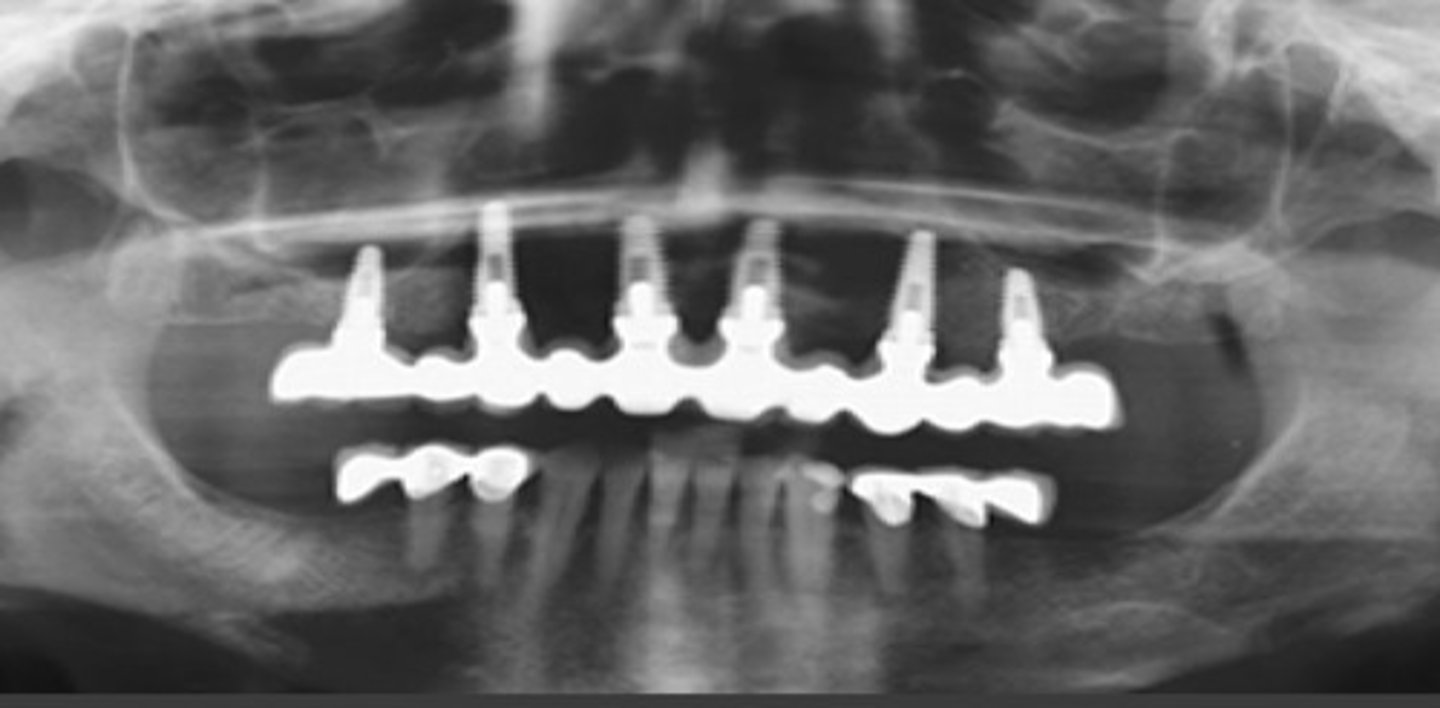

dental bridge with implants

implants